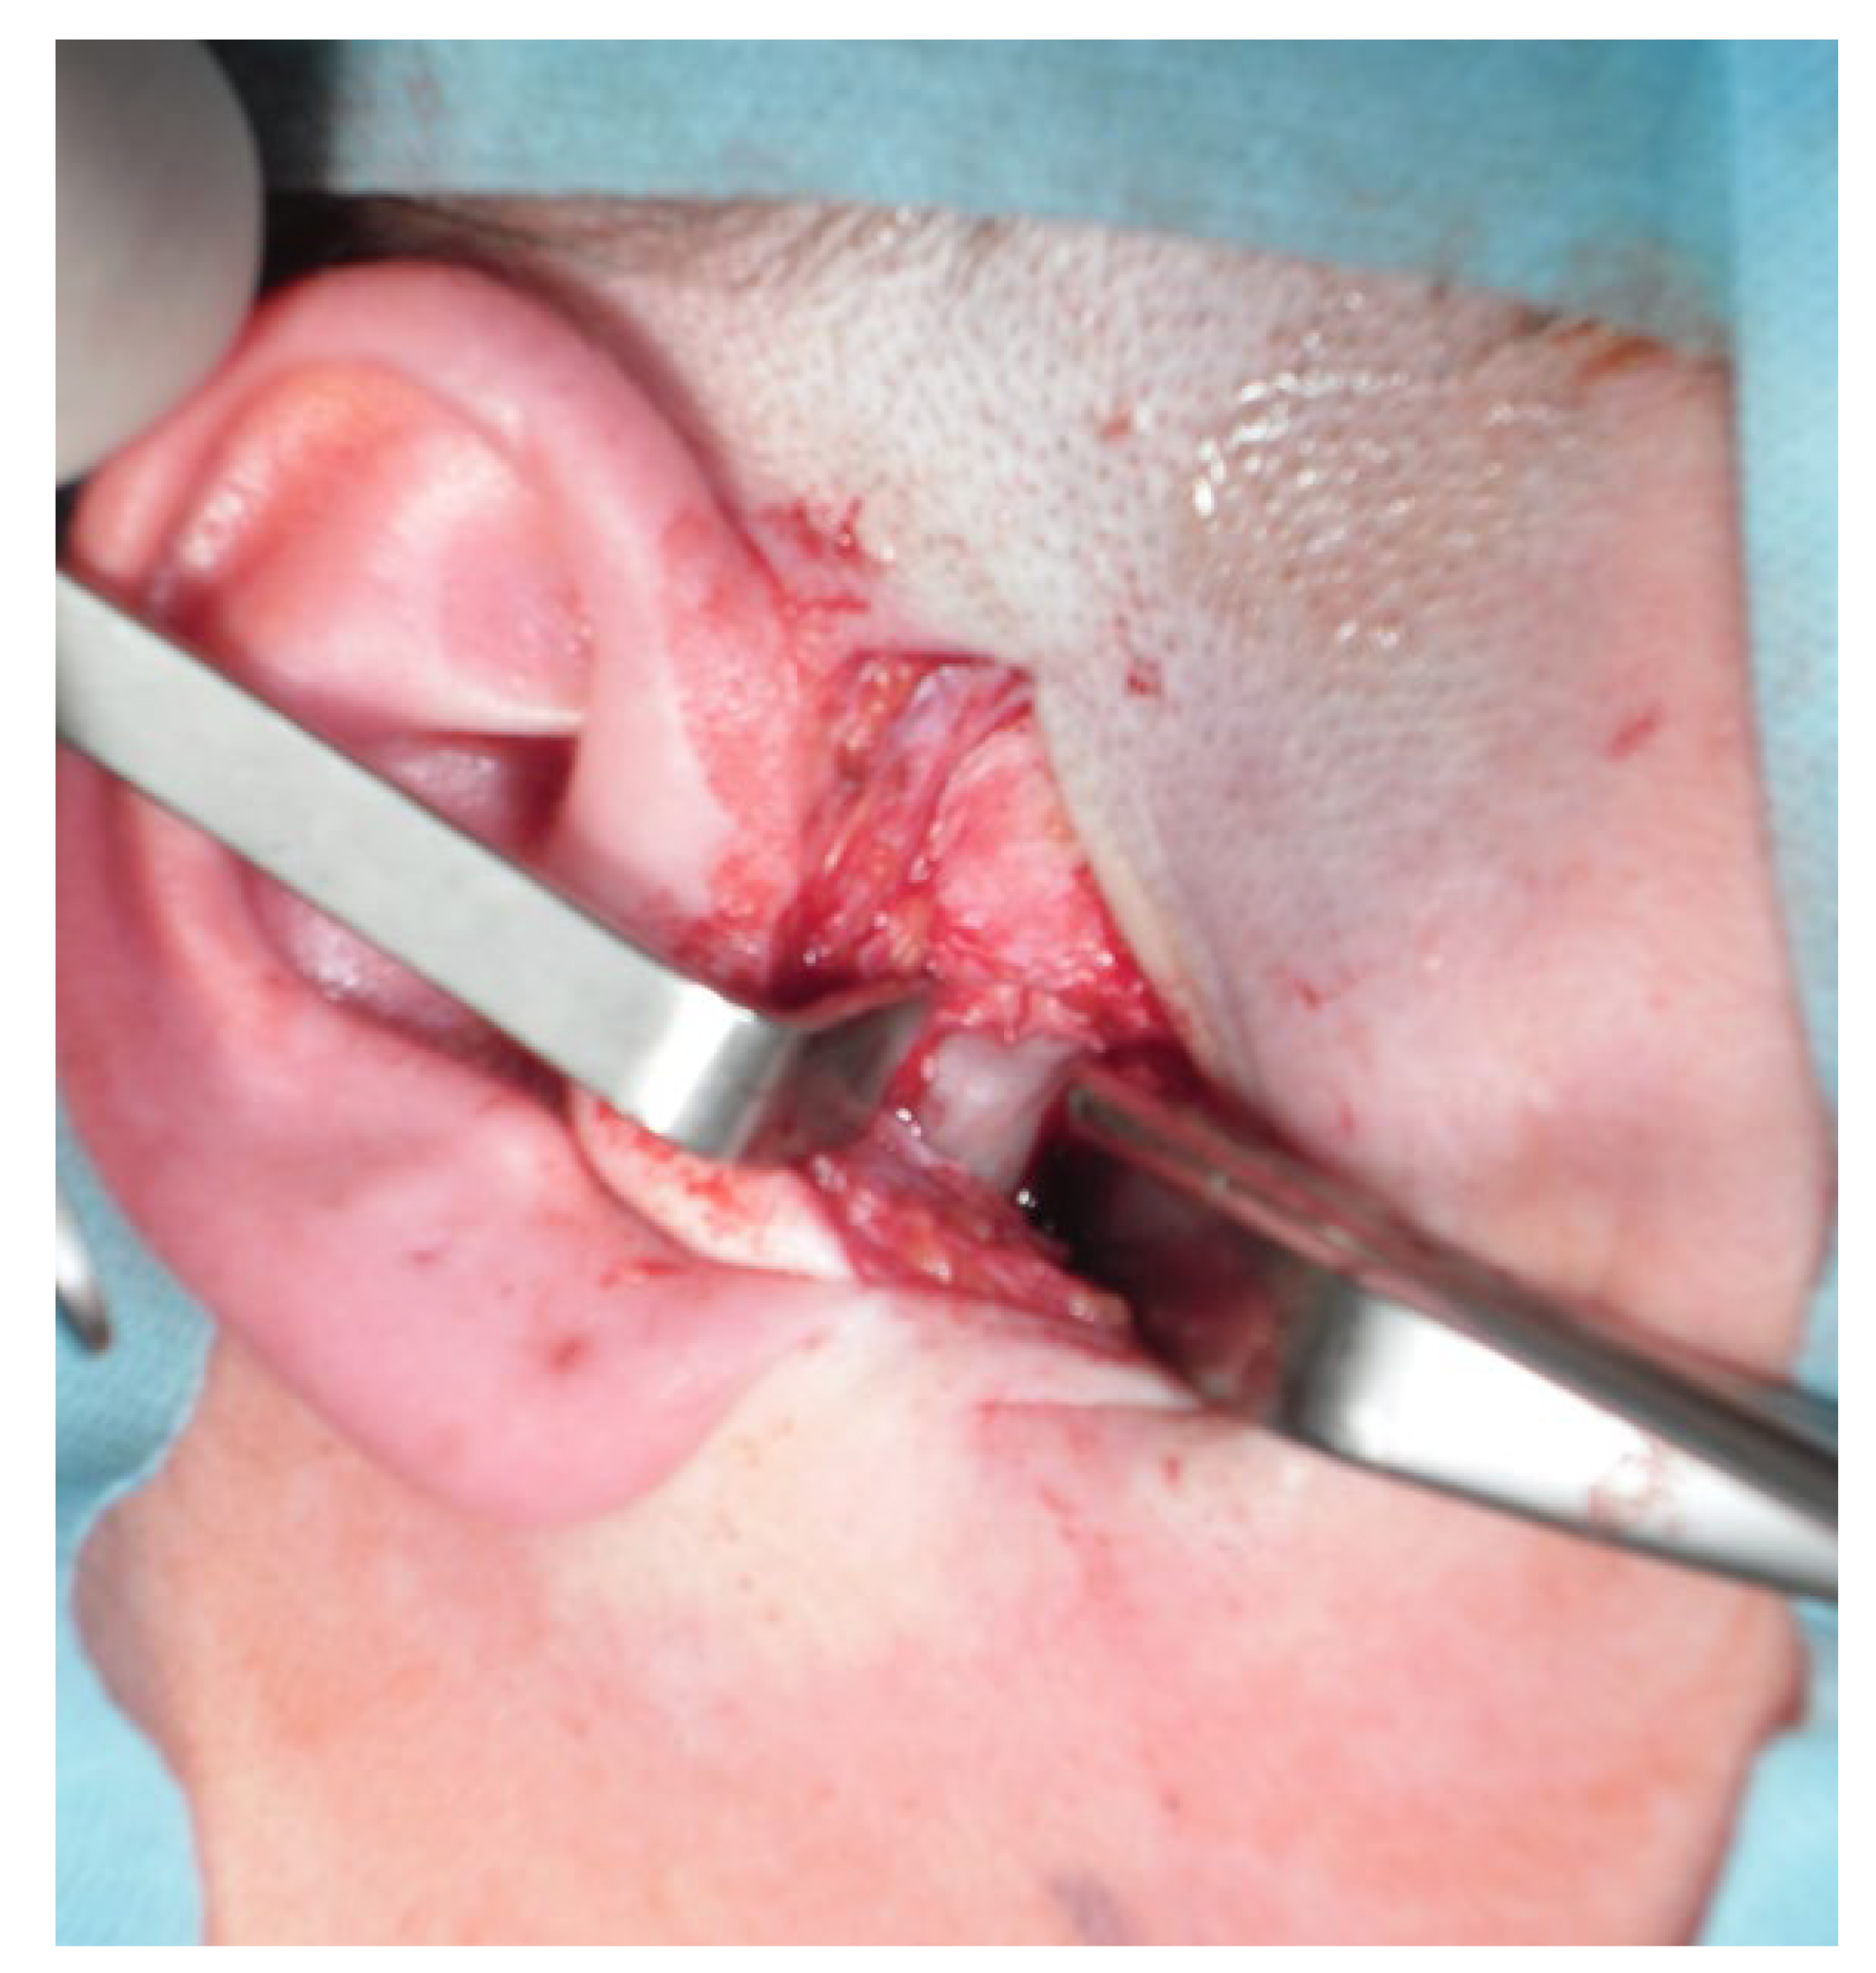

- Transoral approach. This might include techniques with mandibular coronoid process osteotomy to gain more visibility toward the condyle, as reported by Choung et al. [95]. A similar approach to the intraoral approach was described by Wang et al., which might be combined with coronoid process resection and an IVRO procedure–intraoral vertical ramus osteotomy [96,97]. Approaches with computer-guided/3D navigation techniques can also be useful. The intraoral approach for a condylectomy is challenging and can be used in various technique alternations. Some authors combine it with a coronoidectomy, while others combine it with temporal coronoid process osteosynthesis to improve access to the MC. The presented method by Deng et al. described new insights into accurate and safe intraoral approaches [98]. The endoscopic-assisted transoral approach is a similar approach and technique used for intraoral condyle fracture osteosynthesis after fractures and can also be used with a great deal of success to improve intraoral condylectomy [99,100,101].